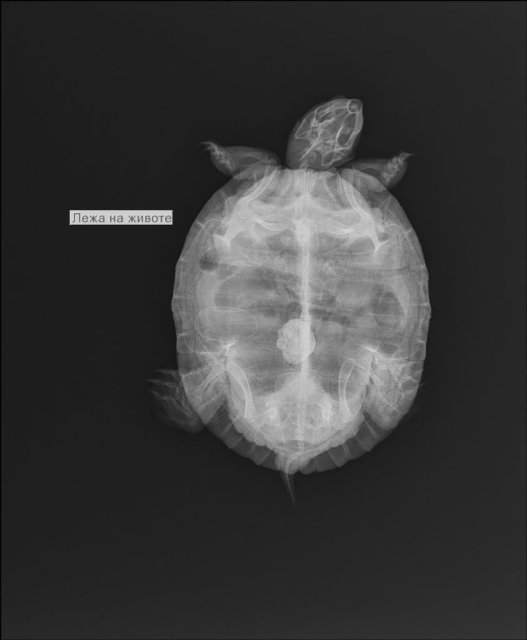

9. Врачей в нашей области нет. Сделали снимок в вет. клинике  в г. Мурманске. Сказали скорее всего инородное тело. Описание снимка делать некому нужных врачей нет. Снимок прикрепила, фото аквариума и черепахи прикрепить не получается превышает объём.

У черепахи яйца и есть шанс, что это не инородный предмет, а отвердевшее яйцо. Нужно чтобы именно врач смотрел.  И вся проблема в том, что она не может снестись, яйца внутри отвердевают/разрушаются и прогнозы у этого без операции неблагоприятные. Да и с операцией никто гарантий не даст, что она выживет.